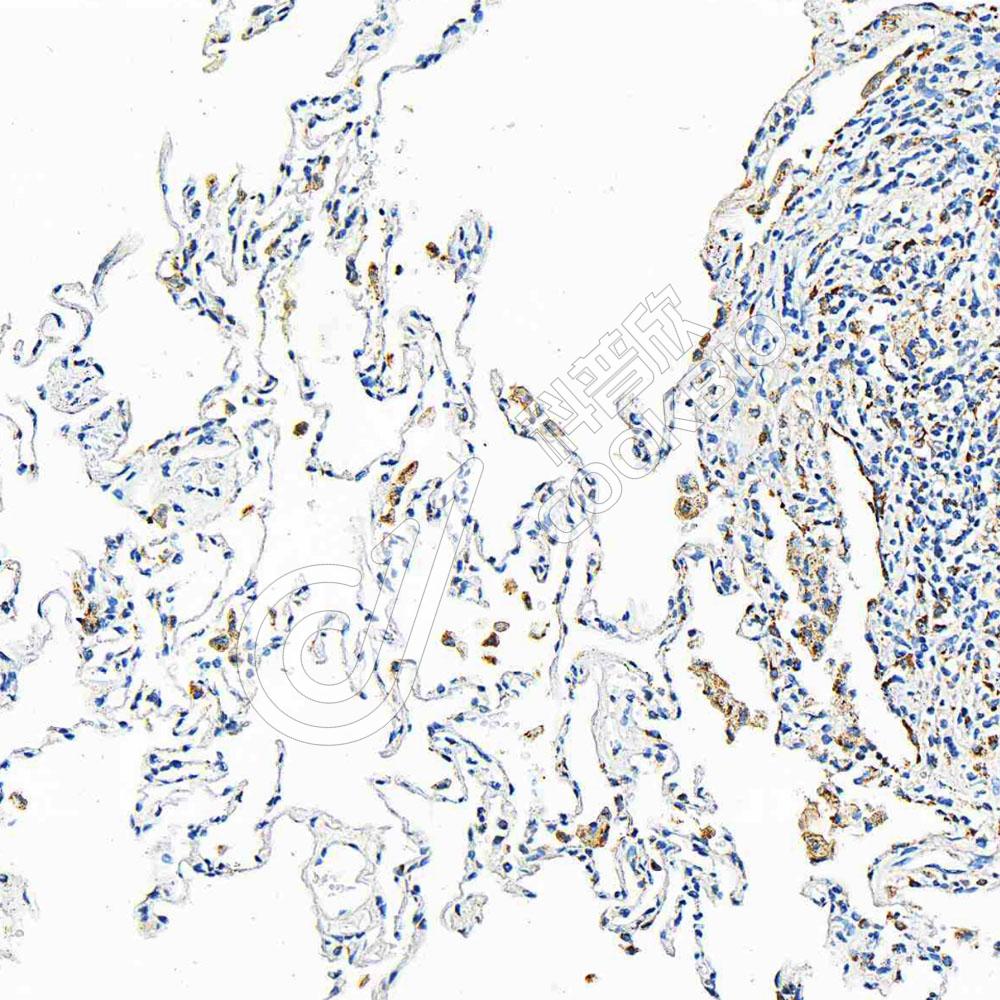

IHC检测CD86蛋白(货号 K1346890).

样品: 人肺, 4%多聚甲醛 (货号KSG1101) 固定12-24小时.

抗原修复: 柠檬酸抗原修复液(干粉, pH 6.0) (KSG1201), 高压锅均匀喷气计时2分钟.

—抗: 1: 300稀释, 4℃ 孵育过夜.

二抗: S-vision免疫组化多聚二抗(山羊抗兔),即用型 (货号KB3906), 室温孵育20分钟.